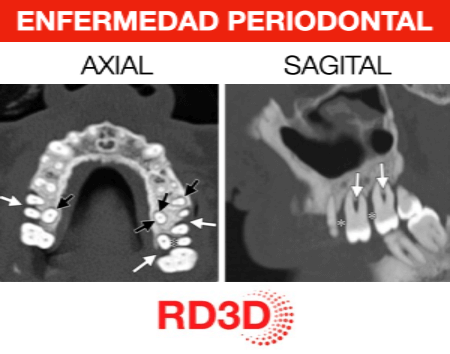

La enfermedad periodontal avanzada no solo afecta a las encías, sino que provoca una pérdida progresiva de hueso que puede comprometer seriamente la estabilidad dental y la planificación de futuros tratamientos. En estos casos, una evaluación radiológica precisa es fundamental. El CBCT (Tomografía de Haz Cónico) se ha convertido en la prueba de imagen más completa para analizar el estado real del hueso alveolar cuando la periodontitis está en fases moderadas o avanzadas.

El CBCT permite una visualización tridimensional del hueso, aportando información clave que no se obtiene con estudios 2D:

- Evaluación precisa de la altura y volumen óseo alrededor de cada diente.

- Identificación de defectos óseos verticales y horizontales.

- Análisis de pérdida ósea en caras vestibulares y linguales.

- Valoración de furcaciones en molares.